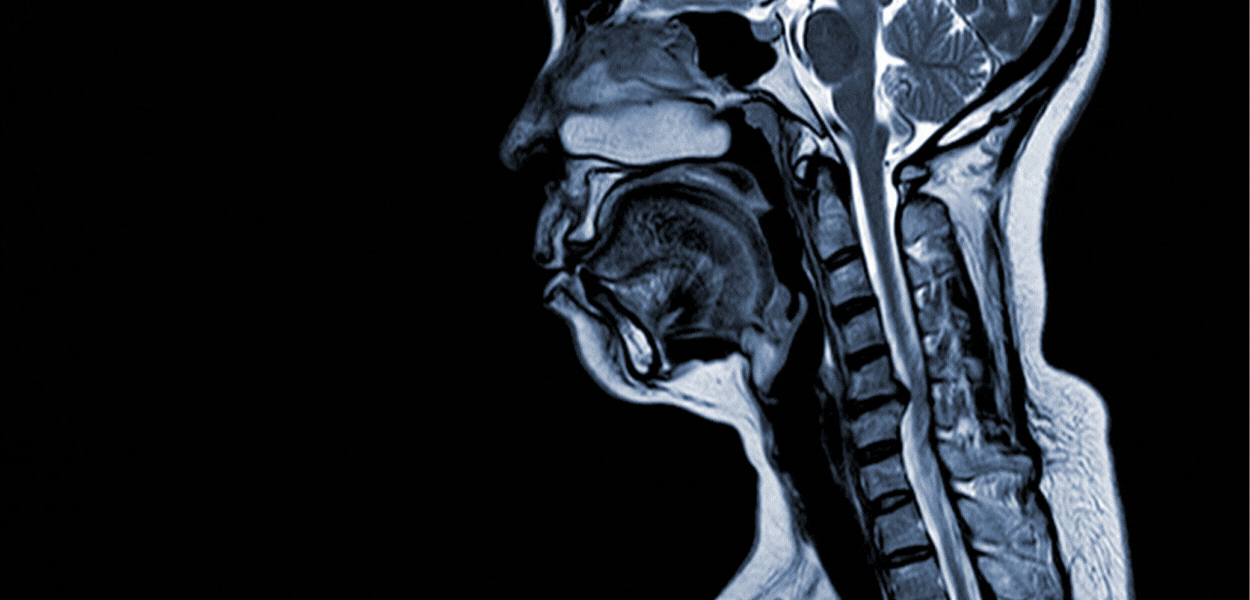

Resonancia Magnética

La Resonancia Magnética, también conocida por la sigla RM es una técnica de imagenología por imagen cuyo funcionamiento se basa en enviar ondas de radio frecuencia que interaccionan con los átomos de hidrógeno del cuerpo mientras están sometidos a un potente campo magnético que rodea al paciente. La RM permite obtener imágenes de gran precisión de distintas partes del cuerpo. Esta técnica imagenológica requiere en algunos casos la administración de medio de contraste paramagnético, para aumentar la sensibilidad diagnóstica.